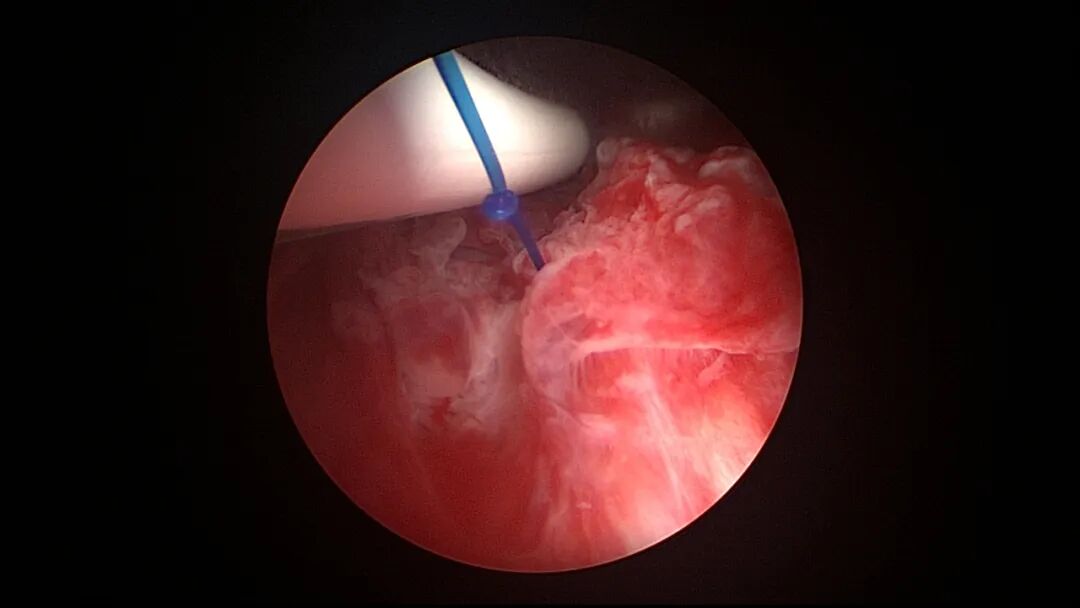

操作步骤描述:宫腔检查镜可完成操作,扩张宫颈至7号扩宫棒,检查镜能轻松通过,避免镜鞘与节育环纵臂在宫颈管形成卡压及筷子效应,影响操作,或卡压摩擦阻力大带出节育环。可用单级电针在宫底扎出小凹坑做标记或作为置入挂钩的隧道(不是必须的)。将挂钩用异物钳直视下送入宫腔,或用中弯钳盲视下送入宫腔,异物钳夹持挂钩将倒钩端插入宫底肌层,越过倒钩。用环尾丝或不可吸收线在节育环顶端打结,形成一个线圈,直径约0.5cm~1cm,结打在线圈旁边,便于夹持操作。将环装回推杆送入宫腔,再夹住节育环固定线圈抵紧宫壁稍旋转就可以将线圈滑进挂钩缺口,挂到挂钩上,可再次向宫底推送挂钩少许,不必夹闭挂钩缺口,重力作用和内膜生长都会阻止线圈脱出,可以用电针电凝挂钩周围组织,进一步防止挂钩脱落。异物钳原位固定节育环,退出宫腔镜,距宫颈外口0.5cm~1cm剪断剩余尾丝。宫颈扩张到9号扩宫棒,冷刀系统异物钳夹持挂钩及线圈也可完成以上操作。

单级电针标记挂钩位置

取胚术后丝线挂钩固定节育环图片及视频

挂钩固定注意事项:月经干净3~7天手术,此时内膜最薄,利于挂钩固定到子宫肌层,如果内膜较厚,最好用负压吸引器去除内膜,暴露基底层,挂钩才能放置到位,也避免内膜掀起、出血等影响操作。挂钩尖端能轻松在子宫壁上粘附,然后调整钳的位置,将挂钩插入到宫底肌层。也可以在体外连接好挂钩和节育环,同时送入宫腔,异物钳在宫腔夹持挂钩并插入宫底肌层。术后复查B超节育环距宫底距离可能较大,个别达3cm左右,跟子宫大、宫壁厚、外加挂钩长度及线圈长度之和较大有关,保持这个距离不再延长即为手术成功。